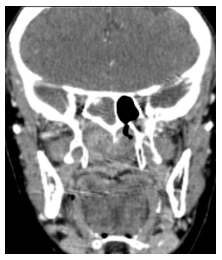

En la Tomografía sin contraste del macizo cráneo facial se aprecia formación de densidad de partes blandas ubicada en fosa nasal y seno maxilar derecho con extensión a senos frontales y celdillas etmoidales, la formación hace protrusión hacia las coanas y Cavum con marcado realce postcontraste (Figura 3).

En la ventana ósea se destacan signos de marcada remodelación ósea predominantemente de los senos maxilar derecho y fosa nasal (Figura 4).